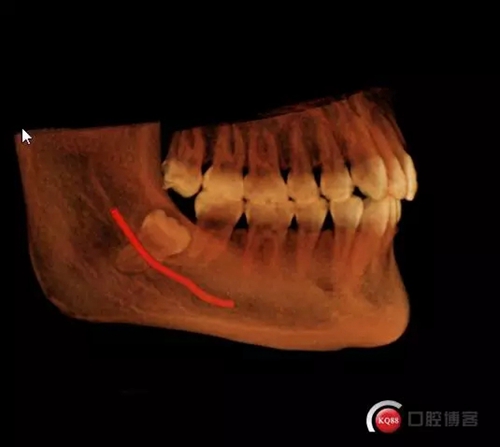

超低位阻生齒緊貼神經(jīng)管伴囊腫

1498615671_453909.png